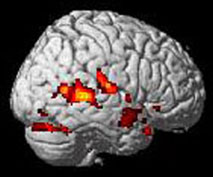

In this interdisciplinary research group, psychologists, cognitive neuroscientists and medical doctors cooperate closely and thereby a broad range of research methods are used for investigations. Functional MRI (fMRI) is a technique to study the functional differences in cognitive processes under well-defined experimental conditions and visualizes activation brain pattern during different kind of stimulation e.g. such as counting tones. Magnetic resonance spectroscopy (MRS) is a method to investigate biomechanically important brain metabolites in defined brain areas non-invasively.  Our work is supported by the DFG, the BMBF and the IMF.